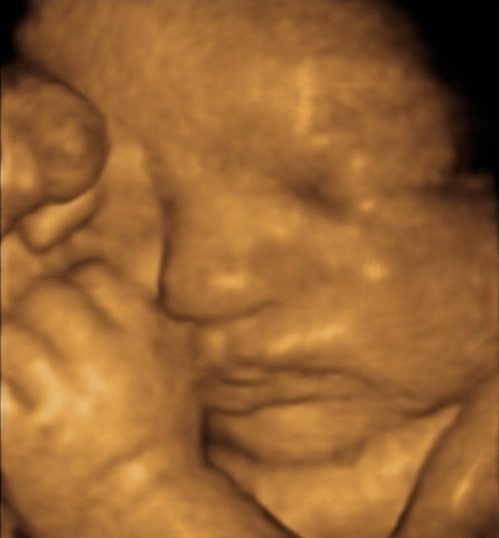

3D and 4D Scan at your antenatal consultation

To provide the highest standard of modern obstetric care, Dr Ken Law has the latest 3D/4D ultrasound scanner right in his consultation room, incorporating modern technologies such as HDLive and skin tone rendering. He offers an ultrasound scan at each of your antenatal visits to see your baby in real-time. This helps you and your partner to start bonding with your baby early, even before he or she is born! He can give you print-outs of your baby’s images, and let you start compiling your baby album before your baby arrives. Dr Ken Law can send you photos and videos via email directly from his ultrasound machine at each appointment. If you are privately insured and eligible for Medicare, there are no out-of-pocket expenses to you for these obstetric ultrasound scans.